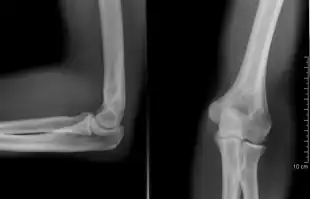

Right: AP X ray of a dislocated right elbow

The types of disease most commonly seen at the elbow are due to injury.

Fractures

There are three bones at the elbow joint, and any combination of these bones may be involved in a fracture of the elbow. Patients who are able to fully extend their arm at the elbow are unlikely to have a fracture (98% certainty) and an X-ray is not required as long as an olecranon fracture is ruled out.[27] Acute fractures may not be easily visible on X-ray.[28]

Dislocation

Elbow dislocations constitute 10% to 25% of all injuries to the elbow. The elbow is one of the most commonly dislocated joints in the body, with an average annual incidence of acute dislocation of 6 per 100,000 persons.[30] Among injuries to the upper extremity, dislocation of the elbow is second only to a dislocated shoulder. A full dislocation of the elbow will require expert medical attention to re-align, and recovery can take approximately 8–14 weeks.